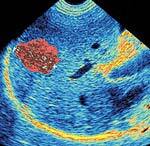

Entering the twenty-first century, one of our greatest health threats is pollutants. Uncounted toxic chemicals pollute what we eat, drink, and breathe. The battle against toxins is largely waged in the liver. Despite being the largest glandular organ, the liver still bears a disproportionate burden in ridding the body of toxins. Those pollutants that cannot be processed and disposed of are stored in fatty tissues, first in the liver and then in other parts of the body. Over time, this can cause long-term harm to the liver. A Powerful Antioxidant Research indicates that in addition to providing toxin protection, N-acetylcysteine is a selective immune system enhancer, improving symptoms and preventing recurrences of common lung-related illnesses such as chronic bronchitis.1 N-acetylcysteine may further protect lung tissue against other conditions through its antioxidant activity.2 Among the most damaging pollutants in the human body are reactive oxygen intermediates. More commonly called “free radicals,” these are the toxic waste products of normal cellular metabolism. Left unchecked, free radicals interrupt the cellular regenerative process, eventually damaging cells. Free-radical-mediated mechanisms have also been suggested as contributing to the development of several neurodegenerative diseases,3,4 and are even suspected of being a major factor in the body’s aging process. Antioxidants scavenge free radicals, effectively neutralizing them and contributing to more-efficient liver function. Antioxidants may also improve food quality and stability by inhibiting the free radical oxidation of food during its processing and storage.5 N-acetylcysteine is a vital antioxidant whose demonstrated beneficial characteristics include the scavenging of potent hydroxyl radicals and diminished production of hydrogen peroxide (H2O2).6

Effects on Glutathione Intracellular glutathione levels affect the ability of lung phagocytes—white blood cells that ingest and destroy bacteria and cellular debris—to do their job properly. Glutathione’s ability to scavenge free radicals enhances cellular function while helping the liver remove chemicals (such as drugs and pollutants) that are foreign to the body. Glutathione is often considered the body’s most important antioxidant because of its location within the cell, which enhances its ability to neutralize free radicals. Increased glutathione levels have demonstrated particularly positive effects on those with severely depleted immune systems, such as HIV patients.7,8 Normal glutathione levels also show promise in the treatment of several lung disorders.9

Oral supplementation with N-acetylcysteine has even been used successfully in two cases to treat a rare syndrome known as pseudoporphyria that complicates kidney dialysis.13 The condition has no other known treatment. The antioxidant activity of N-acetylcysteine helps protect the liver from potentially adverse effects of exposure to a broad range of toxic chemicals, including those chemicals that can poison the body through cumulative use. For example, N-acetylcysteine counteracts acetaminophen toxicity and has been routinely used at very high levels in hospitals for patients with acetaminophen poisoning. It has also been shown to be effective in treating liver failure from causes other than acetaminophen poisoning, including hepatitis and other drug toxicity.14 Supplementation Guidelines N-acetylcysteine has no demonstrated sedative or stimulant effects, and tolerance is excellent for the vast majority of people who take it regularly. As a potentially powerful antidote to our polluted environment, N-acetylcysteine is a simple yet profound way to help protect the body against the ravages of the modern industrialized world. | ||||||||